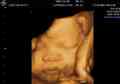

单纯疱疹病毒与怀孕的哪些事,看懂其实怀孕并不难!

单纯疱疹病毒患者是可以怀孕的,但是通常情况下只建议IgG阳性的女性可以怀孕,如果是IgM阳性的女性是不建议怀孕的,不过治疗结束后以后可以正常备孕无碍,但需要注意的是,如果女性在怀孕的时候得了单纯疱疹病毒就很容易根据不同妊娠时间产生不同的影响。,